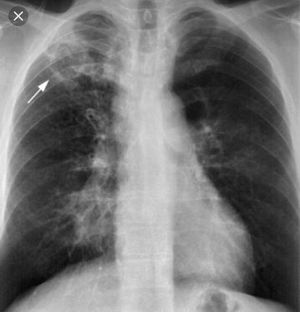

Primary Tuberculosis

Radiology

Pulmonary

Tuberculosis

Tb